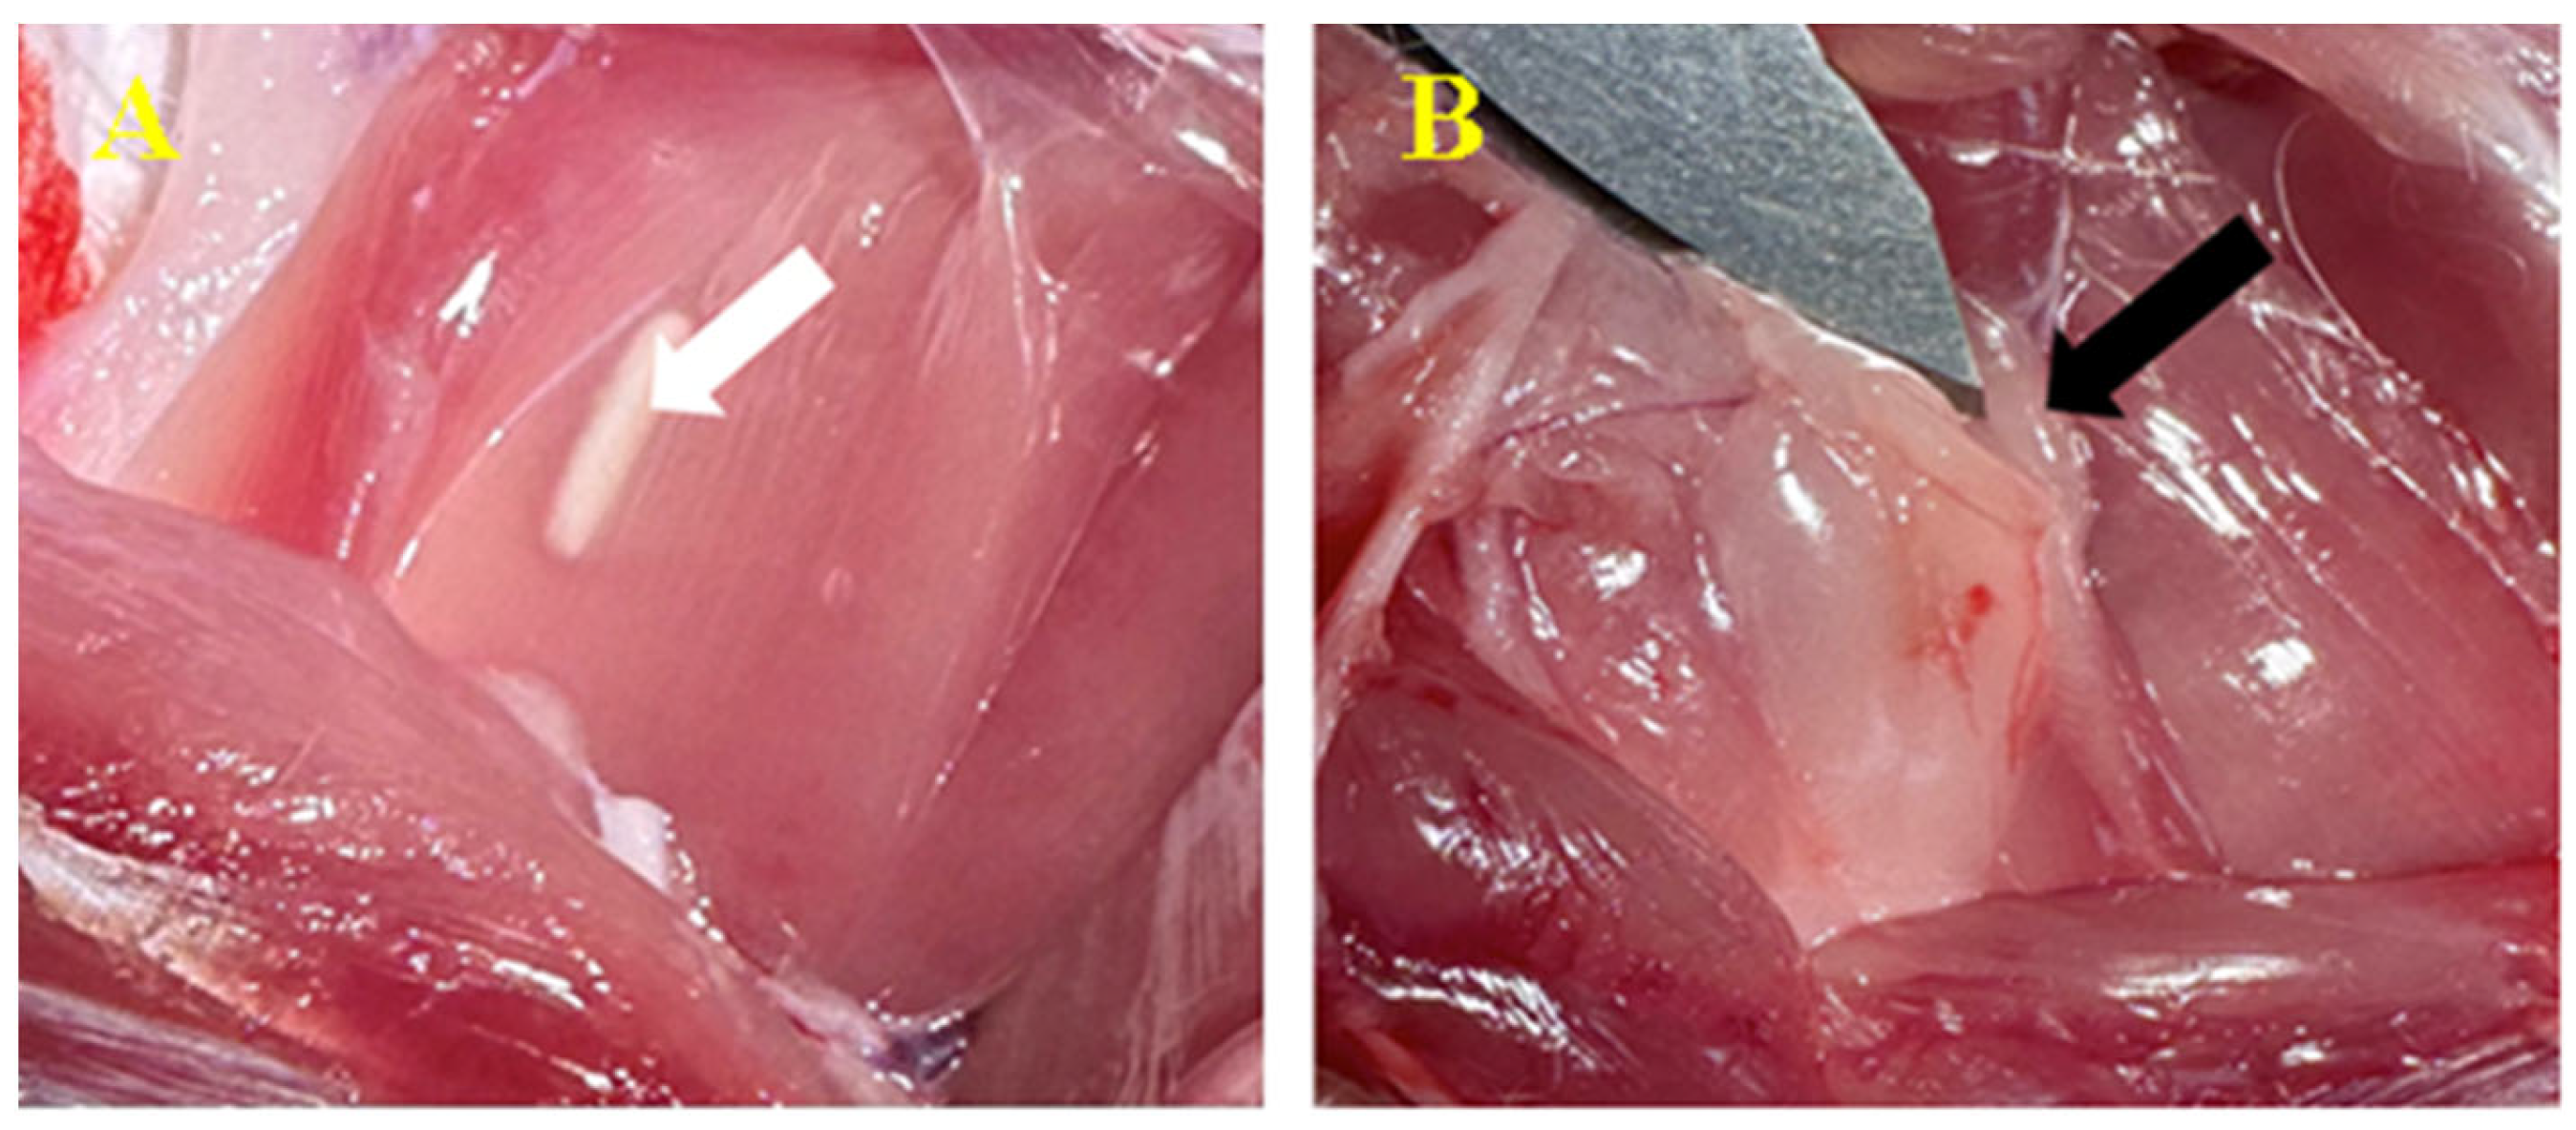

3.3.2. Peri/Intramuscular

3.4. CT Image Findings